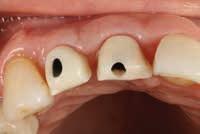

Dental Evidence Recovered: Maxilla and Mandible

To the left is a postmortem rendering created from remains recovered for DCME Case #25-06904/ NamUs #UP144096.

Maxilla Occlusal View

Mandible Occlusal View

Right Left

Right Lateral View

Left Lateral View

Right Left Left Right

Dental Postmortem Radiographs

DCME Case #25-06904: